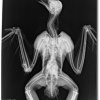

Radiografía evolución de un águila real disparada

Detalle